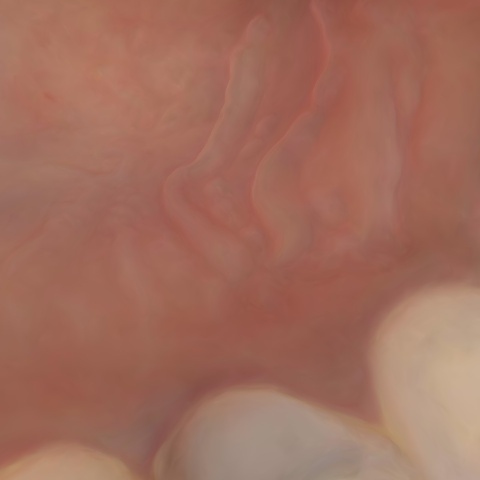

Incorrect Quality Level

The reference annotation for this image is

None

.

Please select the correct quality level.

Annotated as "Good"